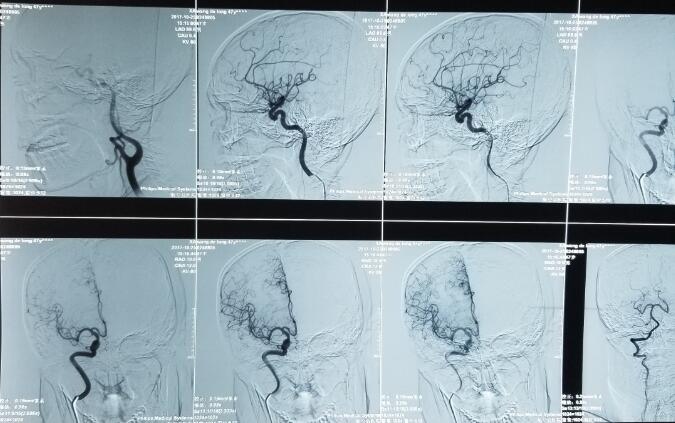

烟雾病又叫Moyamoya病,是一种稀有的脑底血管网反常疾病,首要是因为大脑动脉环双侧首要分支血管(颈内动脉虹吸段及大脑前、中动脉,有时也包含大脑后动脉开端部)缓慢进行性狭隘或阻塞,继发出现侧支反常的小血管网。这些小血管网在脑血管造影时出现许多密布成堆的小血管影,似吸烟时吐出的烟雾,被形象地称为“烟雾病”。烟雾病发患者群呈双峰分布,即十岁以下的儿童和四十岁左右的成年人。据相关材料显现,烟雾病具有必定的区域特性,亚洲是该病的首要发病区域,其间日本、韩国是发病率较高的国家。别的烟雾病作为一种脑血管疾病,具有较高的致残率和致死率,因而烟雾病的医治也成为当下一个亟需处理的问题。

造影下的烟雾状血管